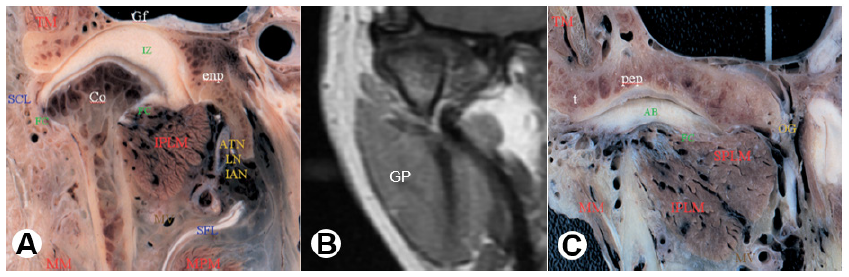

En la figura 7 presentamos tres imágenes en un corte paracoronales anterior a las imágenes de la figura 6 nivel de la parte biconvexa del disco, a los extremos esquemas tipo espécimen y en el medio una imagen en resonancia magnética, donde podemos observar estructuras anatómicas de relevancia como: la glándula parótida (GP), volumen isointenso por detrás y por fuera del borde posterior de la rama, vientre inferior del músculo pterigoideo externo (IPLM), evidenciado por medial del cuello del cóndilo, vientre superior del músculo pterigoideo externo (SPLM) y el disco articular proyectada medialmente (se evidencia isointenso a ligeramente hipointenso por su contenido fibroso) (figura 7).

A: Espécimen en coronal (TM) Músculo temporal, (MM) Músculo masetero, (IPLM) Vientre inferior del músculo pterigoideo externo, (SFL) Ligamento esfenomandibular, (SCL) Ligamento colateral lateral, (Co) Cóndilo mandibular, [(IAN) Nervio dentario inferior, (LN) Nervio lingual, (ATN) Nervio auriculo temporal, en la RM no se evidencia los nervios solo señala el lugar donde estarían], (MPM) Músculo pterigoideo interno. Tomado de: Alomar et al., (15).B: RM en corte coronal (GP) Glándula parótida. C: Espécimen en coronal (SPLM) Vientre superior del músculo pterigoideo externo. Tomado de: Alomar et al., (15).